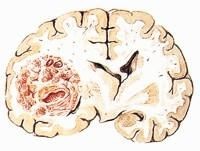

5.转移瘤:既往有肿瘤病史者出现颅内压增高症状和局限定位体征,首先考虑转移瘤。无肿瘤病史,40岁以上人群短期内病情进展迅速,在脑皮质与髓质交界处出现圆形病灶,单发或多发,其密度不均匀,增强扫描示环形强化,可伴有颅骨转移,为破坏性,也应考虑转移瘤。其与脑内病灶有一定距离。多发性转移瘤应与多发性脑脓肿、结核球、淋巴瘤、多发性硬化以及多中心胶质瘤相鉴别。单发转移瘤与胶质瘤、淋巴瘤、脑脓肿鉴别。